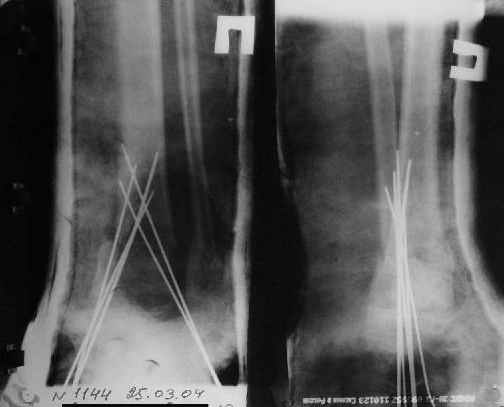

Так как речь зашла непосредственно о травме, см этапные

снимки. Как все было

Первичные

Вытяжение

Нашел в комп-ре схожий случай:

1) з/репозиция, 2) фиксация 2 спицами, 3) аппарат, 4) фиксационные

спицы удалены...

См. аттачт.

А можно было наложить аппарат и по поводу ложного сустава...

По крайней мере не было бы укорочения (пусть и в 2 см)...